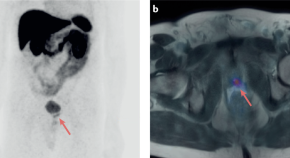

• In this Review, the authors discuss the novel concept of the prognostic role of prostate-specific membrane antigen (PSMA)–PET across all prostate cancer disease states in the context of established prognostic tools and describe the future directions of research on the prognostic value of PSMA–PET.